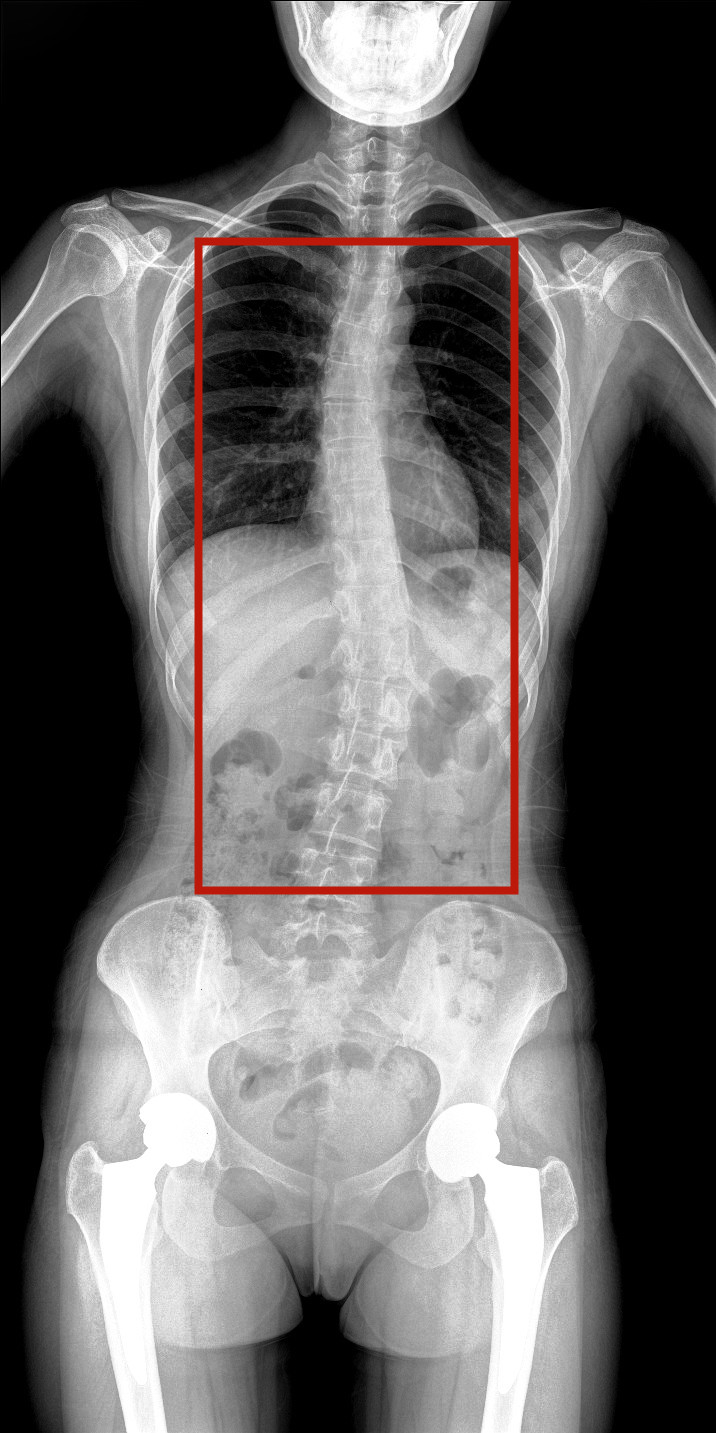

病情描述:患者,女,23歲,免疫系統(tǒng)畸變導(dǎo)致的脊柱側(cè)彎

虛線框示患者脊柱側(cè)彎明顯

脊柱圖像范圍包含脊椎、雙側(cè)肩部及骨盆。片內(nèi)頸椎、胸椎、腰椎、骶椎、雙肩及骨盆重組影像結(jié)構(gòu)清晰,對比度高,對位、對線好,接緣區(qū)無重疊、遺漏、縫隙。能夠滿足臨床測量脊柱Cobb角及臨床人體平衡線等指標(biāo)的測量,整體上能對全脊柱進(jìn)行觀察診斷。